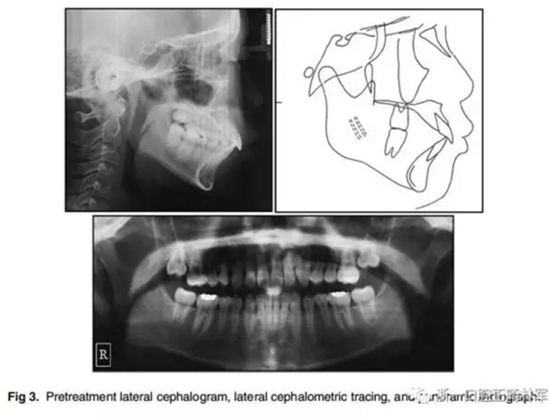

1.口內(nèi)像(Fig 1)、研究模型(Fig 2)和全景X光片(Fig 3)顯示了輕度牙列間隙,覆牙合覆蓋較大,右上第一前磨牙扭轉(zhuǎn)。覆牙合為4.0 mm,覆蓋為5.5 mm,兩側(cè)有輕微的Ⅱ類磨牙關(guān)系。除了上頜第二磨牙以外的所有牙齒都已經(jīng)萌出,患者口腔衛(wèi)生不良,有廣泛的牙齦炎癥,但牙槽骨未吸收。顳下頜關(guān)節(jié)形態(tài)良好,沒有癥狀。

2.在面部照片(Fig 1)中,患者嘴唇嚴(yán)重前突。治療前的側(cè)位X線片(Fig 3,Table)顯示ANB角較大(7.6°),上頜骨突出(A至N距離5.8 mm)和下頜骨后縮(Pog至N垂直距離,-5.6 mm)。上下頜中切牙唇傾(U1 to FH,122.2°,IMPA,106.2°)。美國正畸學(xué)指標(biāo)差異指數(shù)評分為30分?;颊呒捌涓改敢庾R到他的下頜骨比上頜骨小得多,他的母親說,由于兒子身材矮小,他很快就開始接受生長激素(GH)治療。他的身高是154厘米,遠低于他那個年齡的平均水平,位于倒數(shù)的的10%。